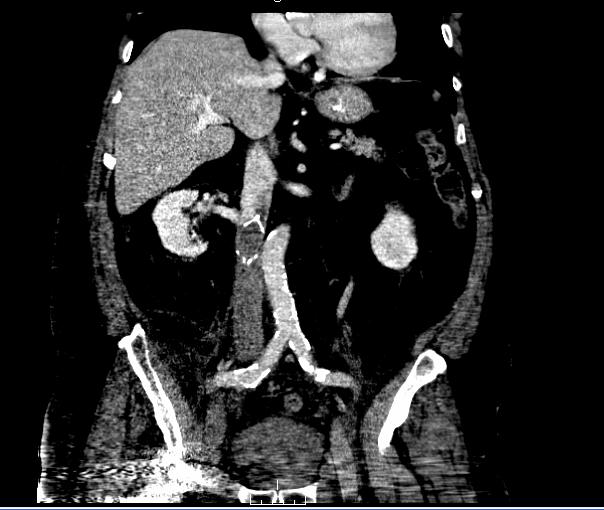

- Perforation – Sometimes, an IVC filter may perforate through the inferior vena cava into adjacent structures. In most cases this happens after time has elapsed from the filter insertion. This may be due to filter struts breaking or twisting or after filter migration and burrowing through the IVC wall.